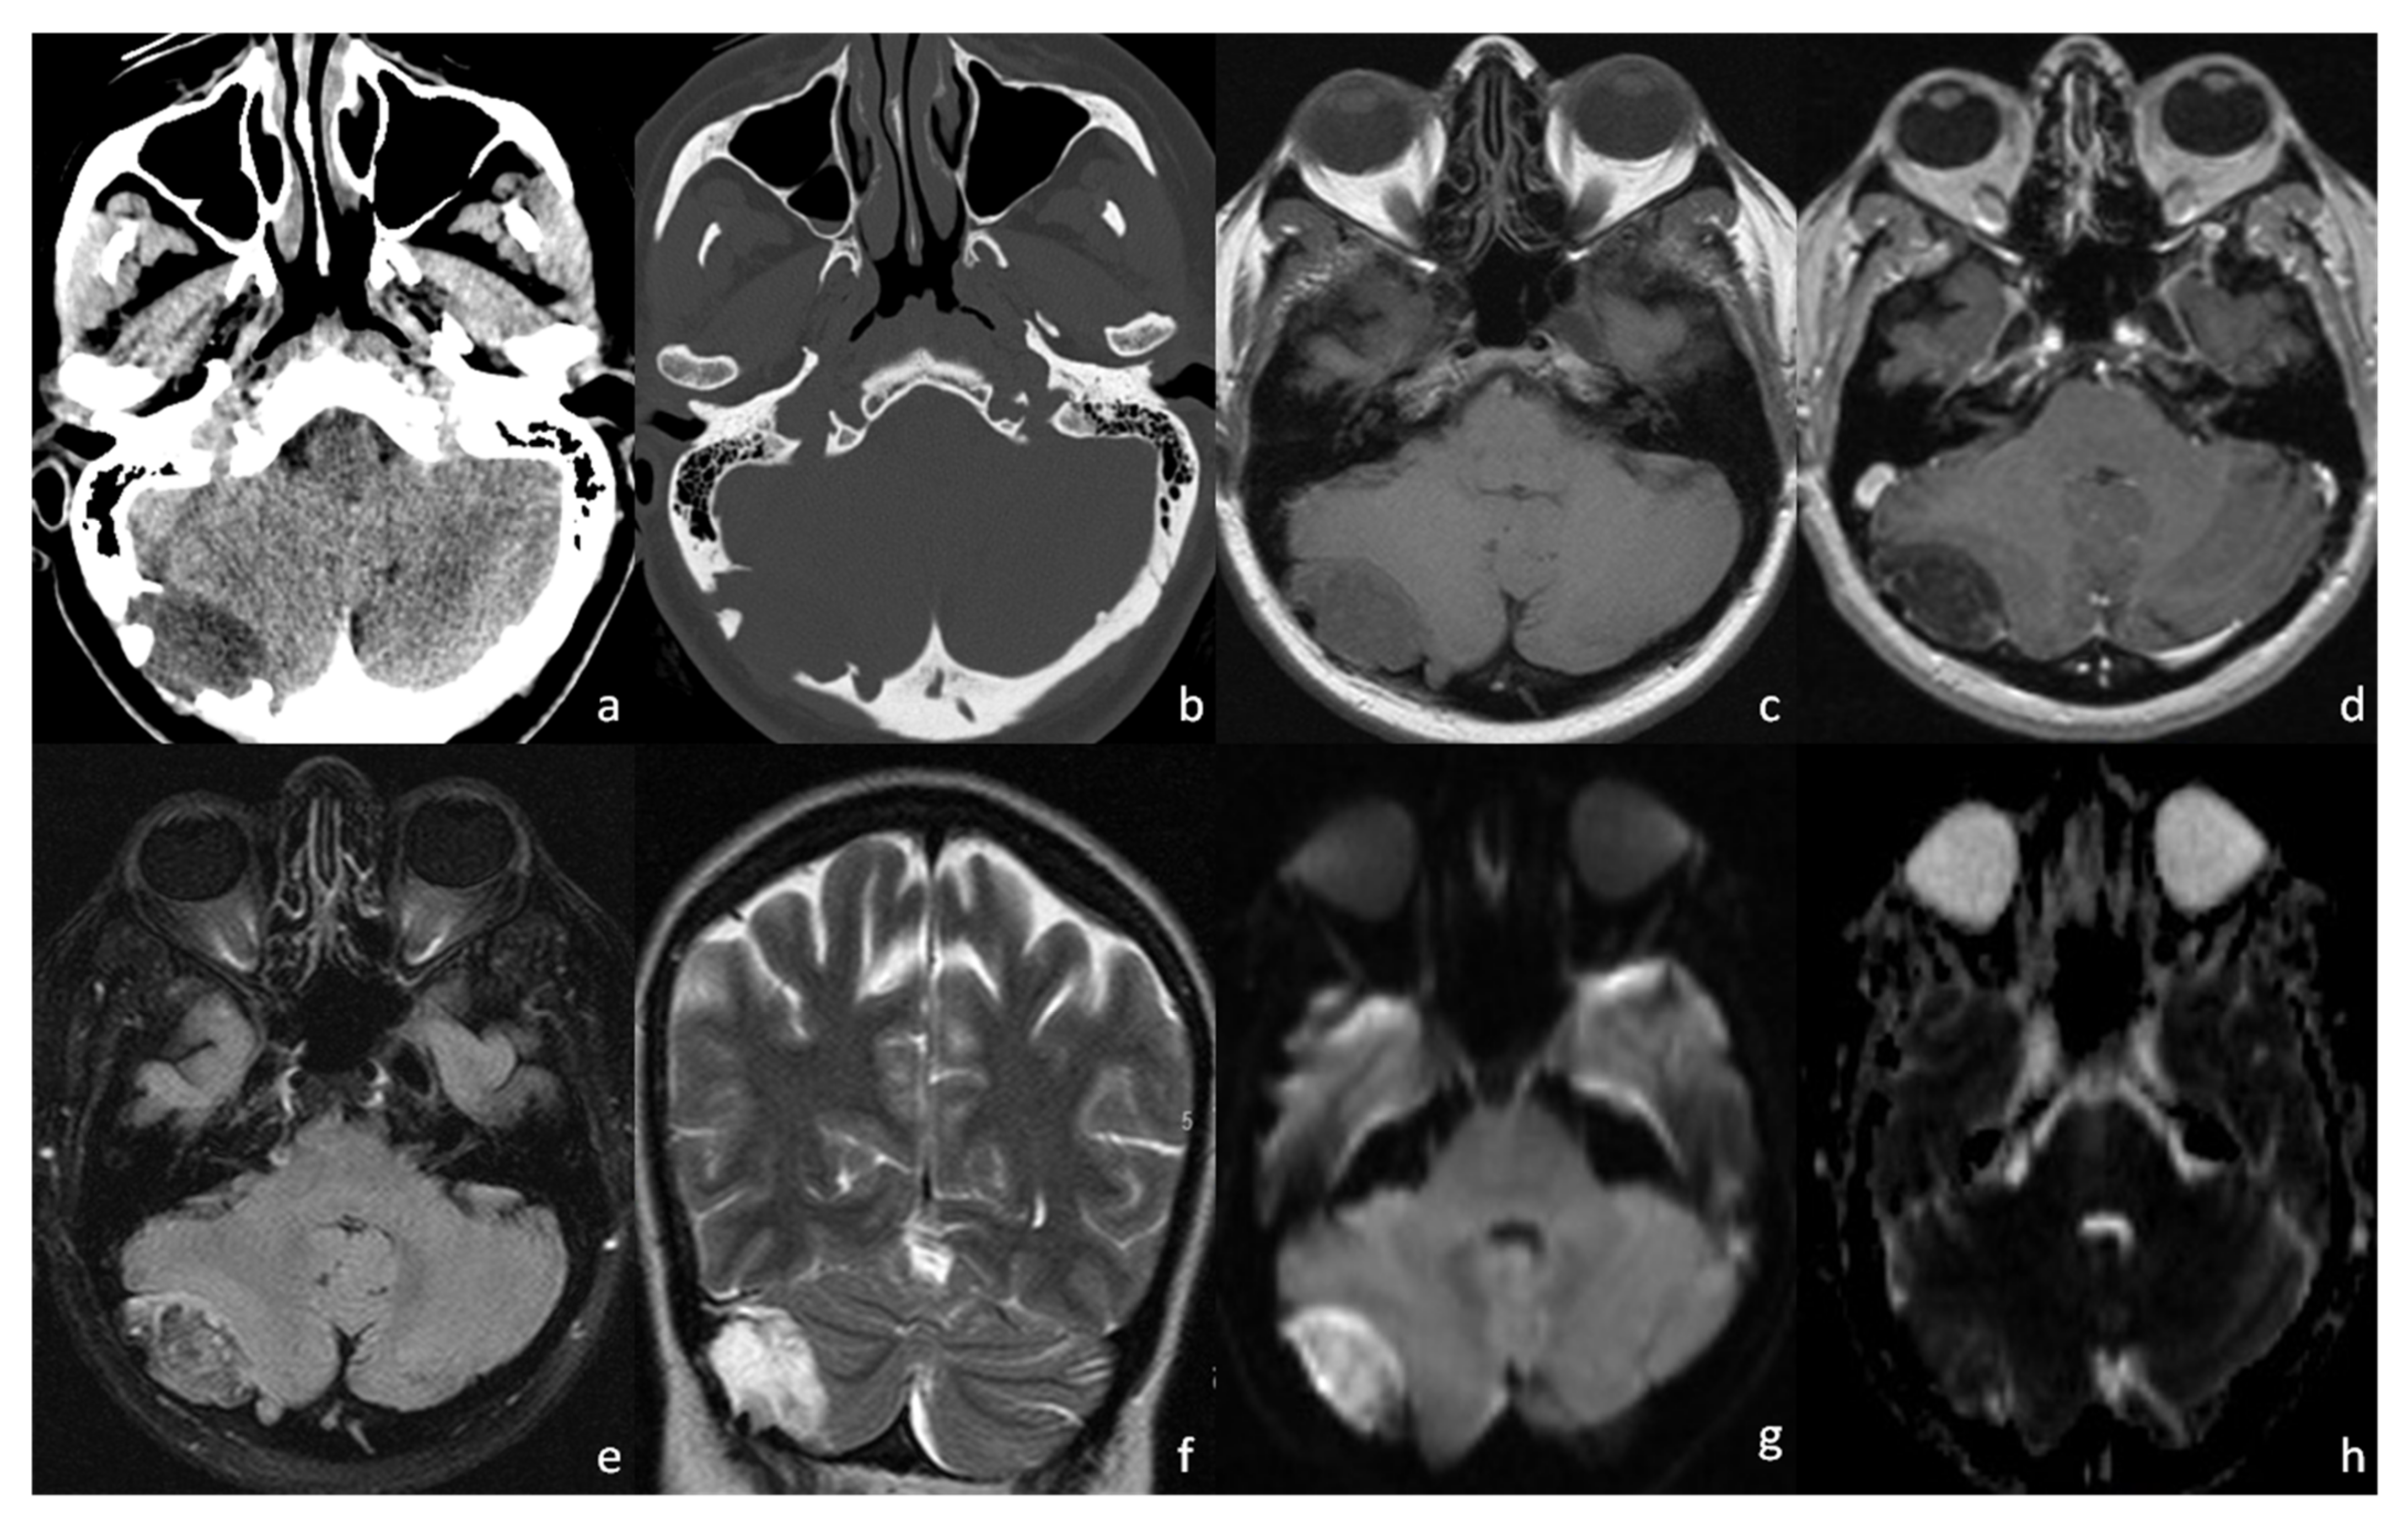

2. Case Presentation